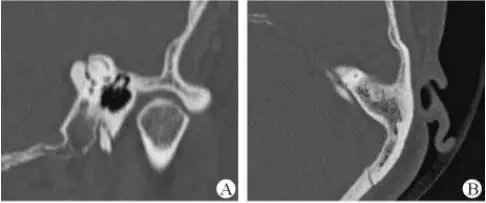

1、上半規(guī)管裂綜合征

內(nèi)耳結(jié)構(gòu)非常微妙。即使是內(nèi)耳中大頭針樣的孔洞也能造成平衡失調(diào)。患者常常不敢進(jìn)行如走路或轉(zhuǎn)頭的日常活動。此罕見疾病,醫(yī)學(xué)專家預(yù)估至少影響著人口的1%。可造成惡心,眩暈以及對噪聲極高的敏感性。病人還常常抱怨他們能聽到血管跳動的聲音。其中一位患者曾告訴耳科專家,他都能聽到自己轉(zhuǎn)動眼睛的聲音。

診斷及治療

醫(yī)生若懷疑此病將會安排內(nèi)耳CT掃描。在大多數(shù)案例中,一旦此病被耳鼻喉科醫(yī)生或其它聽力健康專家確診,則可實行手術(shù)治療。外科手術(shù)風(fēng)險包含聽力損失以及神經(jīng)損傷;重建及復(fù)原需內(nèi)耳的治療以及大腦的重塑。

2、膽脂瘤

另一個不常見的疾病叫膽脂瘤,發(fā)病率為1/10000,這個“腫瘤”在內(nèi)耳中逐漸生長。盡管不是惡性的,但也能導(dǎo)致永久性的聽力損失以及其它嚴(yán)重的疾病,比如腦膜炎。癥狀是有臭味的耵聹以及聽力損失。